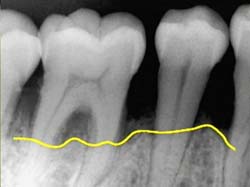

歯周病の原因は、歯に付着したプラーク(歯垢)に含まれる「歯周病菌」が、歯周組織を次々に破壊し骨まで溶かしてしまう病気です。歯周病は、症状が進むまで痛みもほとんど発生しないため、気がついたら既に手遅れとなっており、歯を支える骨(歯槽骨)が溶けてしまい、歯を失ってしまいます。

歯肉炎→歯周病(第1段階→第2段階→第3段階)

歯周基本治療を行っても歯周ポケットが残り、歯周ポケットの深さが4mmを超えるような場合に行います。